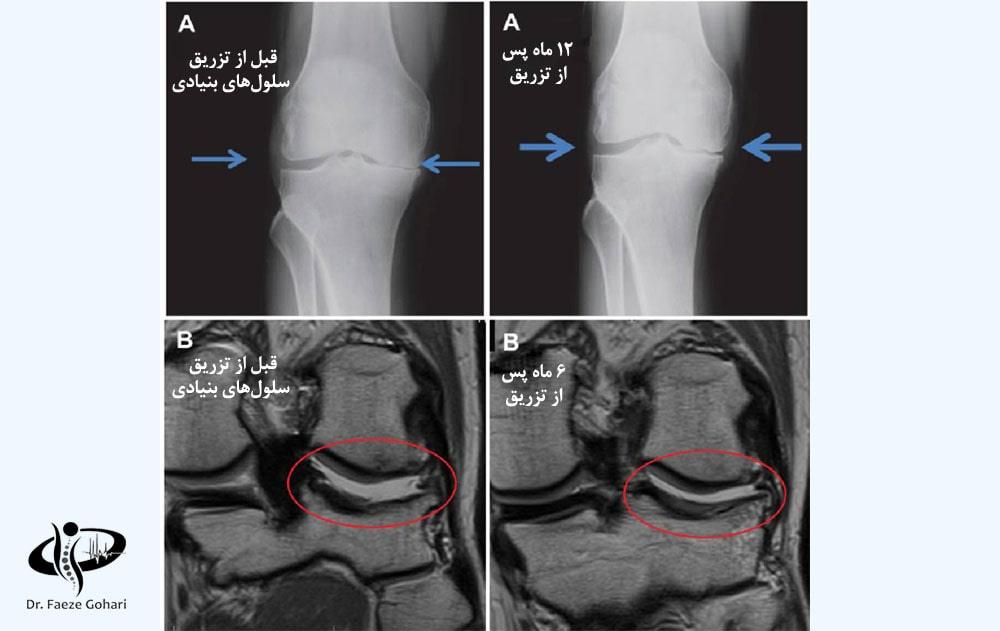

تصویر بالا مربوط به بیمار مبتلا به آرتروز زانو است که درمان با تزریق سلولهای بنیادی را دریافت کرده است. نتایج این درمان پس از ۶ ماه و ۱۲ ماه بهوضوح قابلمشاهده است. این نتایج شامل بازسازی غضروف، کاهش ساییدگی استخوانها، بهبود عملکرد مفصل و کاهش تورم و التهاب در ناحیه آسیبدیده است.